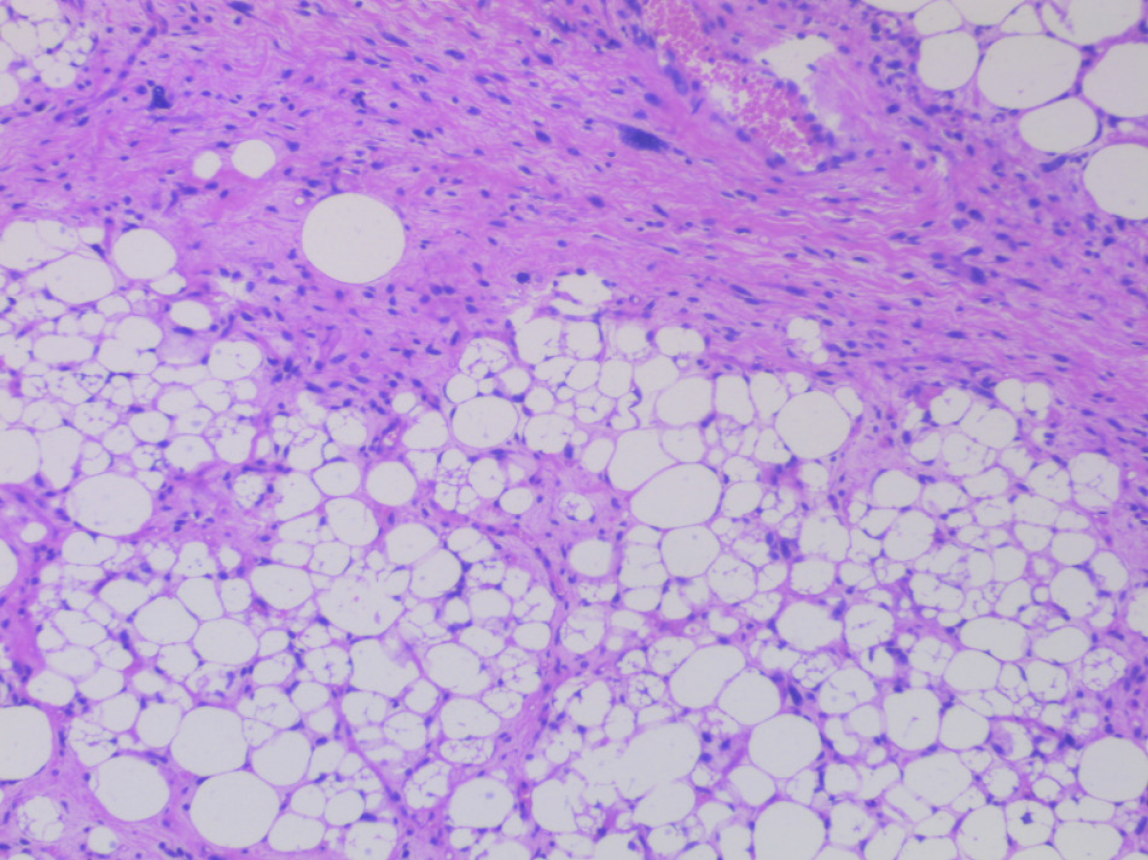

Figure 3 Hematoxylin and eosin staining showing atypical spindle-shaped cells in the tumor (original magnification × 100).